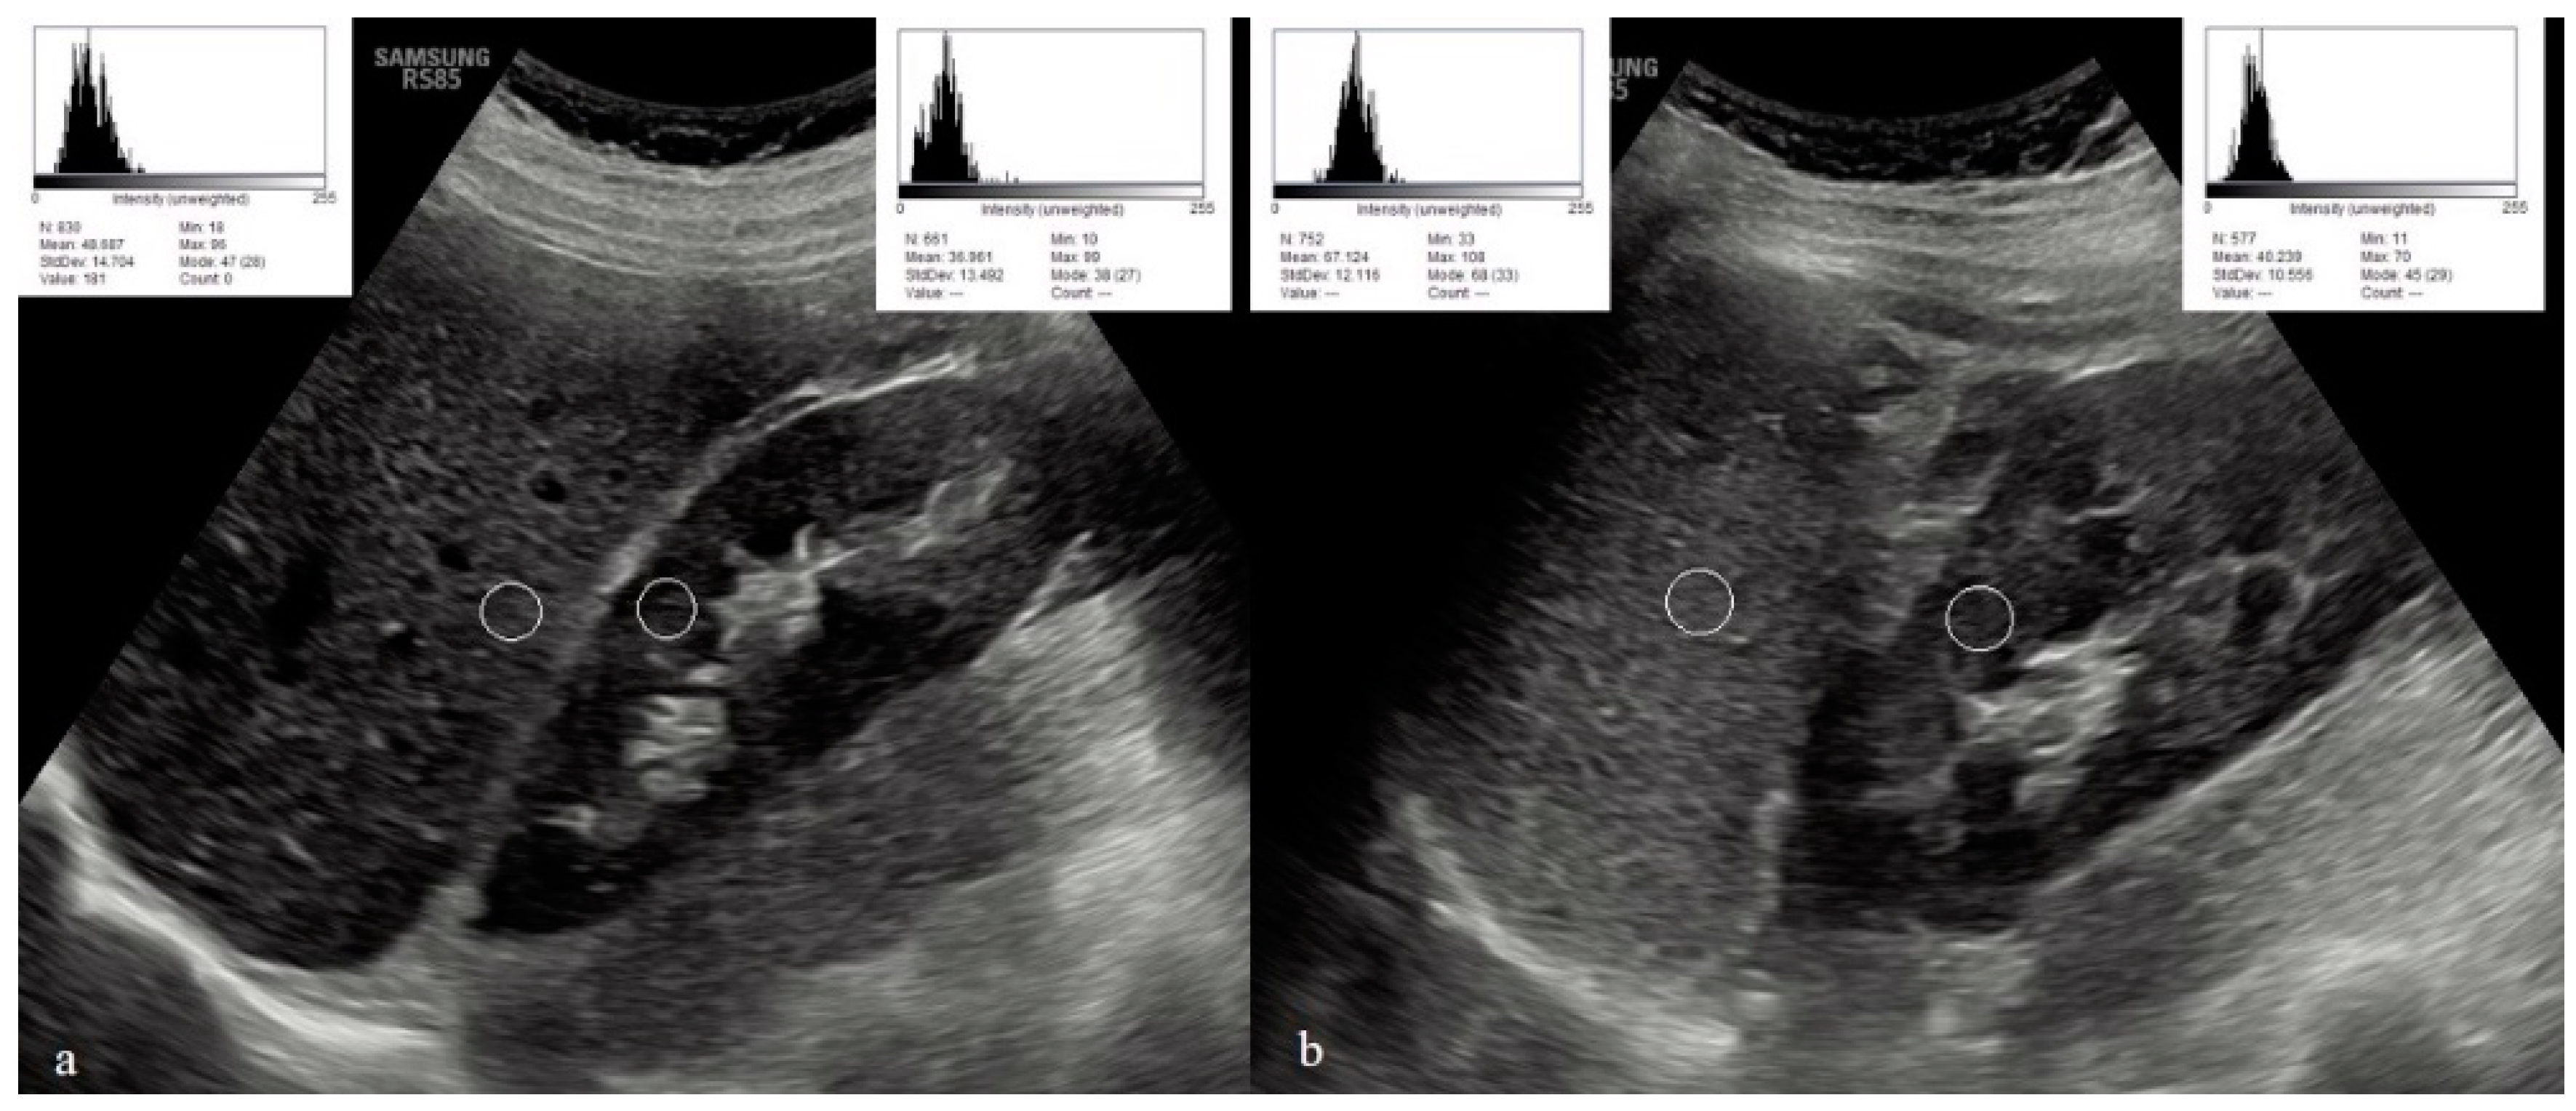

| Right renal echointensity % | 59.6 (44.6–80.8) | 32.7 (28.7–52) | <0.001 |

| Left renal echointensity % | 58 (41.4–83.5) | 33.9 (29.1–58.7) | <0.001 |

| Spleen echointensity | 35 (31–39) | 35 (31–57) | 0.62 |

| Hepatic/renal echointensity ratio % | 1.43 (0.44–2.2) | 1.9 (1.05–3.3) | 0.025 |